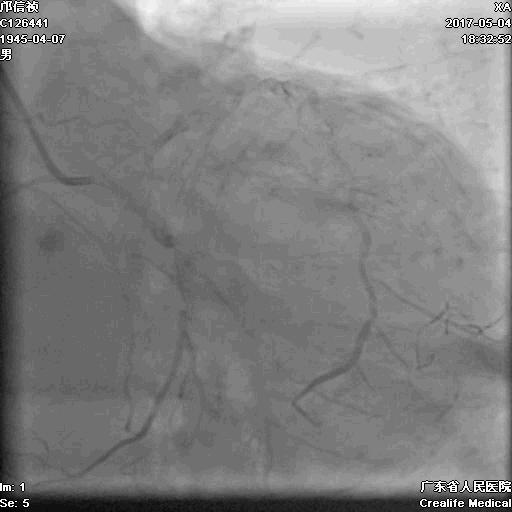

冠脉造影

基本资料

Syntax score 37.5